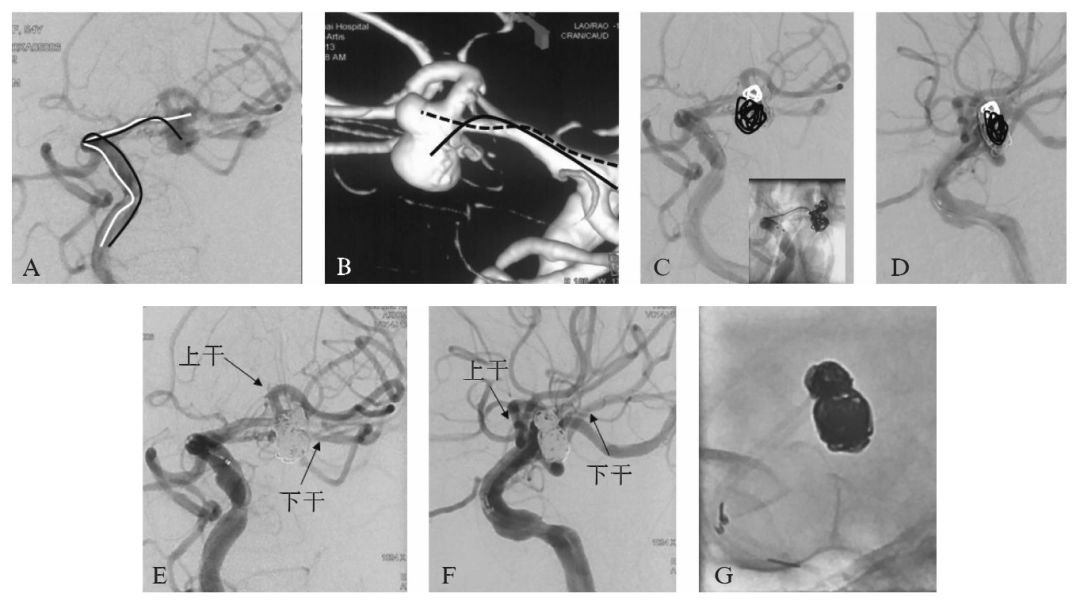

患者,55岁,女性,因“头痛3周”就诊,MRI检查可见右侧丘脑出血后陈旧性软化灶(图10-1A、C),左侧侧裂池内T1WI及T2WI可见局部血管流空影(图10-1B、D),进一步MRA检查证实左侧大脑中动脉动脉瘤(图10-1E)。

图10-1 患者入院前MRI及MRA检查

A,C:右侧丘脑出血后T1WI低信号,T2WI高信号的陈旧性软化灶(箭头);

B,D:左侧侧裂池内T1WI及T2WI可见局部血管流空影;

E:头颅MRA证实左侧大脑中动脉动脉瘤

MRI、MRA:头颅MRI平扫可见右侧丘脑出血后的T1WI低信号,T2WI高信号的陈旧性软化灶(图10-1A、C),同时左侧侧裂池内T1WI及T2WI可见局部血管流空影(图10一1B、D);MRA证实左侧大脑中动脉动脉瘤,动脉瘤呈分叶状,形态欠规则(图10-1E)。